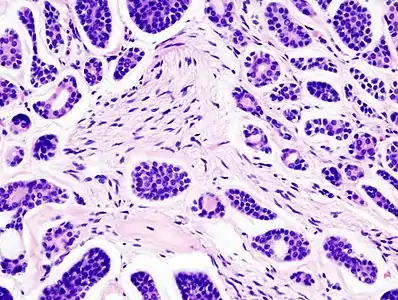

| Micrograph of an adenoid cystic carcinoma of a salivary gland (right of image): Normal serous glands, typical of the parotid gland, are also seen (left of image), H&E stain. | |